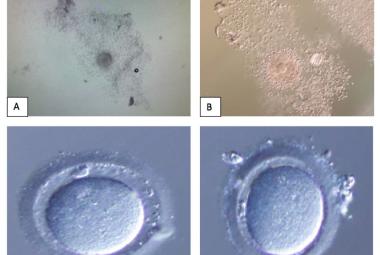

Parkinson’s disease (PD) is a neurological condition affecting the motor functions of the brain, characterised by the degeneration of dopaminergic neurons in the substantia nigra pars compacta region. The primary symptoms include dyskinesia, bradykinesia and resting tremors. This study investigated the potential impacts of Mitragyna speciosa or known as kratom on zebrafish with PD. 1-methyl-1,2,3,6-tetrahydropyridine (MPTP) solution was administered intraperitoneally to zebrafish to develop Parkinson’s symptoms in 2 to 3 days, followed by three concentrations treatment of kratom, for 28 days. On day 28, locomotor behaviour was evaluated to determine the duration spent in the top, middle, and bottom zones, total distance travelled and swimming speed. Then, the zebrafish were euthanised and preserved in a 10% formalin solution. Fixed zebrafish were processed and embedded in paraffin blocks for haematoxylin and eosin, and cresyl violet staining. The results of treatment groups showed that kratom had a neuroprotective impact, increasing time spent from bottom to top zone, distance travelled and swimming speed compared to the negative group. Moreover, the treatment groups experienced a rise in neuron regeneration and an enhancement in neuron appearance following a 28-day exposure to kratom. In conclusion, kratom shows promise as a potential treatment for PD by effectively reducing symptoms and improving movement.

Penyakit parkinson adalah keadaan saraf neurologi yang mempengaruhi fungsi motor otak yang dicirikan oleh degenerasi neuron dopaminergik pada bahagian substantia nigra pars compacta. Gejala utama penyakit ini termasuklah diskinesia, bradikinesia dan gegaran berehat. Kajian ini dijalankan untuk menyiasat potensi kesan kratom terhadap ikan zebra dengan penyakit parkinson yang dihasilkan. 1-methyl-1,2,3,6-tetrahydropyridine (MPTP) diberikan secara intraperitoneal kepada ikan zebra untuk mewujudkan gejala parkinson dalam tempoh 2 hingga 3 hari, diikuti dengan rawatan tiga kepekatan Mitragyna speciosa yang berbeza selama 28 hari. Pada hari ke-28, tingkah laku lokomotor dinilai untuk menentukan tempoh masa yang dihabiskan di tiga zon yang berbeza iaitu zon atas, tengah dan bawah, jumlah jarak perjalanan dan kelajuan berenang. Kemudian, ikan zebra dimatikan dan diawet dalam larutan formalin 10%. Seterusnya, ikan zebra diproses dan dibenamkan dalam blok parafin untuk pewarnaan hematoksilin & eosin dan Cresyl Violet. Keputusan kumpulan rawatan menunjukkan bahawa kratom mempunyai kesan neuroprotektif, meningkatkan masa yang dihabiskan dari zon bawah ke zon atas, jarak perjalanan dan kelajuan berenang berbanding kumpulan negatif. Selain itu, kumpulan rawatan mengalami peningkatan dalam penghasilan semula neuron dan peningkatan dalam penampilan neuron berikutan rawatan selama 28 hari menggunakan kratom. Kesimpulannya, kratom menunjukkan potensi besar sebagai rawatan alternatif untuk penyakit parkinson dengan mengurangkan gejala secara berkesan dan meningkatkan pergerakan lokomotor.